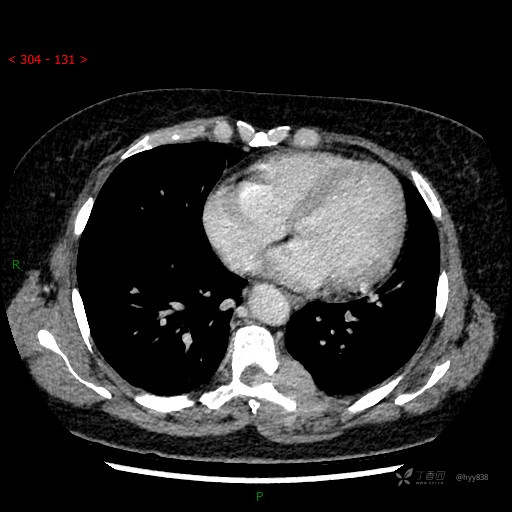

胸部CT平扫